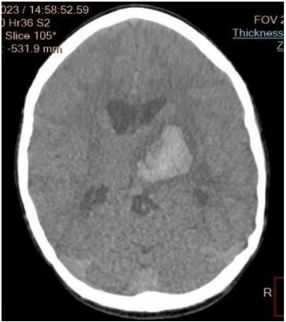

Subsequent computed tomography (CT) of the brain revealed a hyperdense lesion 2.9x4.1cm of blood density in the left parietal lobe involving the thalamus suggestive of hematoma (Fig 4). The computed tomography of the chest showed cardiomegaly with laevocardia, common atrium connected to the right and left ventricle separately, right-sided aorta connected to the right ventricle, pulmonary artery connected to the left ventricle, left-sided inferior vena cava (IVC) draining both upper and lower left part of the body directly into the common atrium on the left side, single right-sided superior vena cava (SVC) draining the right upper part of the body into the common atrium on the right side (Fig 5). The upper abdomen revealed transposition of the major visceral organs. There are two main hepatic veins (with 3 branches, each) joining before draining direct to the common atrium (CA) (Fig 6)

Figure 4: CT scan of the brain showing left cerebral hematoma at the levelof the thalamus.